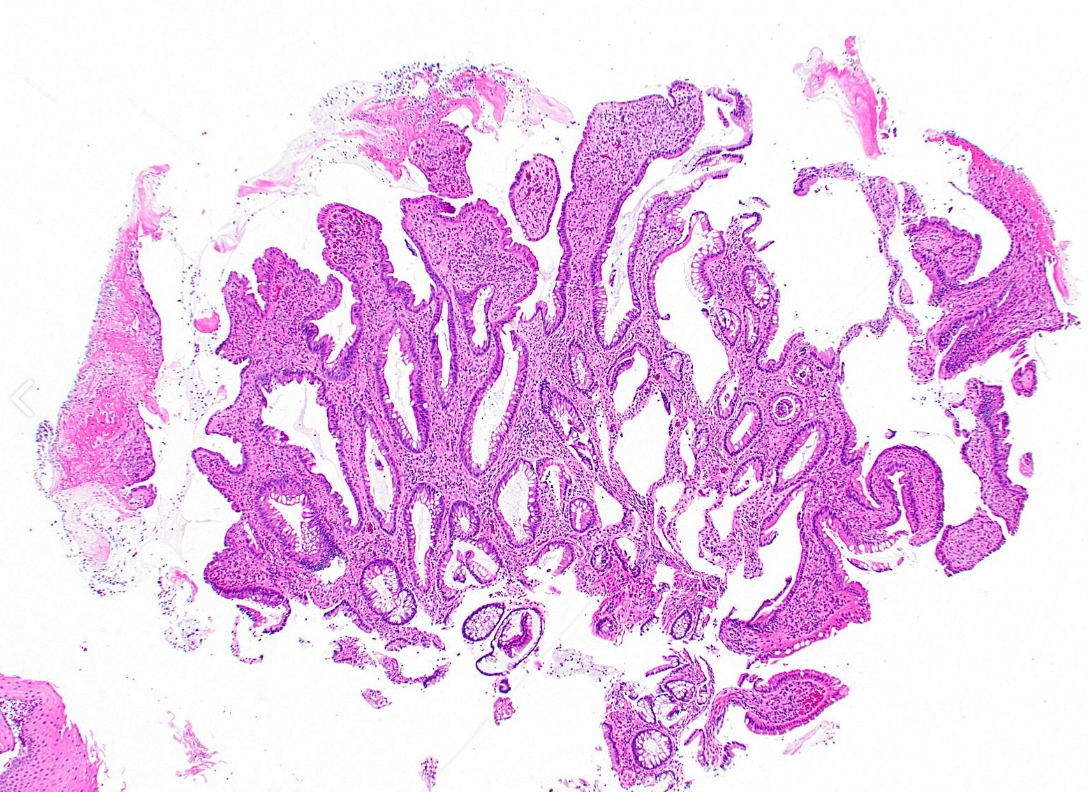

75M rectal polyp

dx

Key features

Traditional serrated adenoma

The two most distinctive features of TSA are the slit-like serration, reminiscent of the narrow slits in the normal small intestinal mucosa, and the tall columnar cells with intensely eosinophilic cytoplasm and pencillate nuclei. Ectopic crypt formations, defined as epithelial buds not anchored to the muscularis mucosae, are always found along the sides of the villous projections of protuberant TSA, but they are rarely present in (and are not necessary for the diagnosis of) flat TSA { 26001333 }. Most TSAs contain only scattered goblet cells, although a mucin/goblet cell–rich TSA has been described { 28295534 }. An adjacent precursor polyp, either an MVHP, GCHP, or SSL, is found in as many as 50% of TSAs { 25589791 }. Like in SSL, areas of overt dysplasia can be found in TSA { 25216220 ; 24225759 ; 24603588 }. This superimposed dysplasia is described as either intestinal or serrated type

Below: note multiple ectopic crypt foci